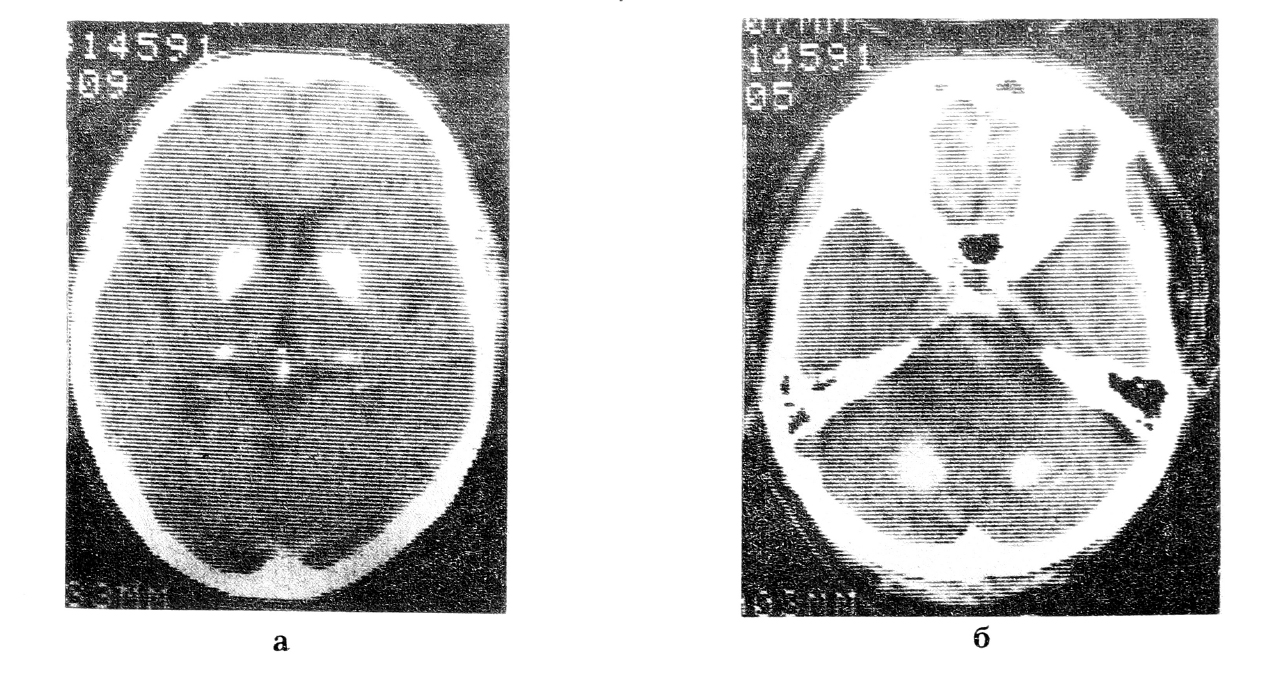

Компьютерная томограмма головы больного В.: а) двустороннее обызвествление базальных ядер; б) обызвествление в полушариях мозжечка

КТ: в области подкорковых структур большого мозга и в обеих гемисферах мозжечка визуализируются симметрично расположенные гиперинтенсивные очаги, по плотности соответствующие кальцификатам. Умеренно расширены субарахноидальное пространство и боковые желудочки.

Итак, наличие симметричных обызвествлений головного мозга, локализующихся в базальных ганглиях и гемисферах мозжечка, клинически проявляющихся экстрапирамидными, мозжечковыми нарушениями, эпилептическими припадками, позволяет диагностировать синдром Фара.